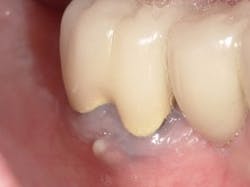

Most fistulas are endodontic or periodontal in nature. The appropriate specialist referral is possible with endodontic gutta percha (GP) points. As they appear radiopaque on x-rays, threading an open fistula can help confirm the origin of its source. Every office should have a vial of 30-gauge GP for this reason. First, break the point in half so that during an x-ray the patient does not accidentally bite down on it. Using cotton pliers, gently guide the point through the fistula until there’s resistance. A radiograph can then be used to determine the next course of action. Don’t be fooled and assume the source. Many times, a GP point will veer off in a surprising direction.